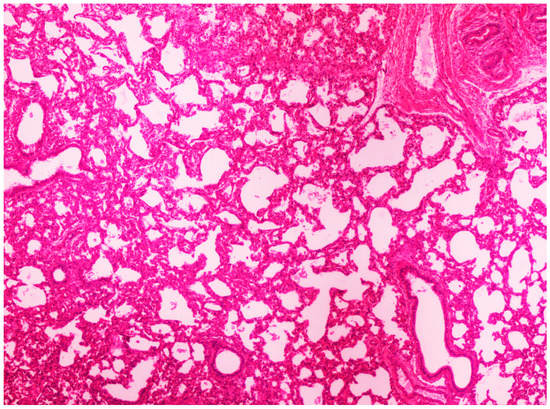

3.3.2. Histopathological Lesions

3.3.3. Scanning Electron Microscopy (SEM) Findings